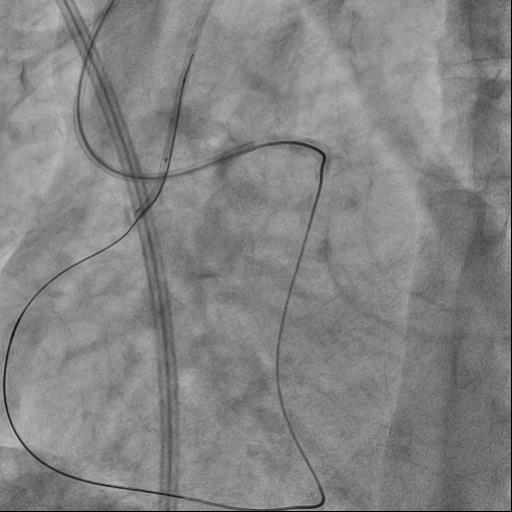

The guide catheter was selectively placed at the RCA orifice, several attempts at antegrade recanalization were performed, after 10 minutes a decision was made to perform retrograde recanalization of the RCA, Sion Blue with the support of a Corsair 150cm microcatheter was successfully introduced through the septal branch into the middle segment of the RCA, escalation to Gaya 2 was performed and recanalization of the RCA was performed. Tip-In was performed in the antegrade guide catheter, the retrograde coronary guide was fixed with a balloon catheter. The retrograde microcatheter was advanced into the proximal segment, however, when performing Corsair, its defragmentation occurred, and the tip of the microcatheter itself was torn off. A decision was made to perform repeated recanalization of the RCA in a new lumen. Recanalization was successfully performed, then Tip-In was performed into the antegrade microcatheter and its successful passage beyond the occluded area. Balloon angioplasty and stenting of the RCA under OCT control with vFR.

A) Antegrade progress during recanalization of the orifices of chronic occlusion of the coronary artery is important, however, changing the tactics to retrograde recanalization, when it¡¯s absent, may further facilitate antegrade advance of the coronary guidewire, since the retrograde guidewire serves as a control point. B) If the retrograde intracoronary guidewire is well-controlled in the antegrade guide catheter, it is safer to use the tip-in technique in the antegrade microcatheter. It is preferable to perform the tip-in at the bend in the guide catheter, since both devices (the micro catheter and the coronary guidewire) are in the same plane.